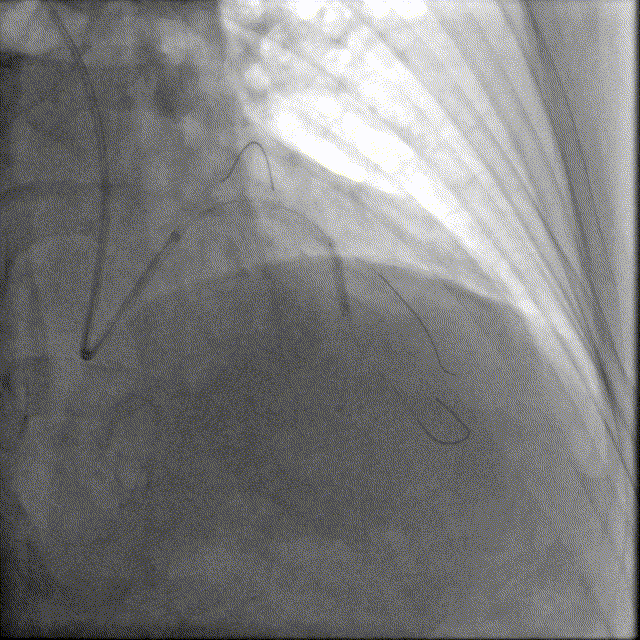

造影如下

患者左主干前三叉1,0,1型病变,主干末端偏心40%狭窄;前降支病变自开口延续至中段,口部80%狭窄,中段80%狭窄,病变位置钙化严重;回旋支近段约30%轻度狭窄,第一及第二钝缘支开口80%局限病变。